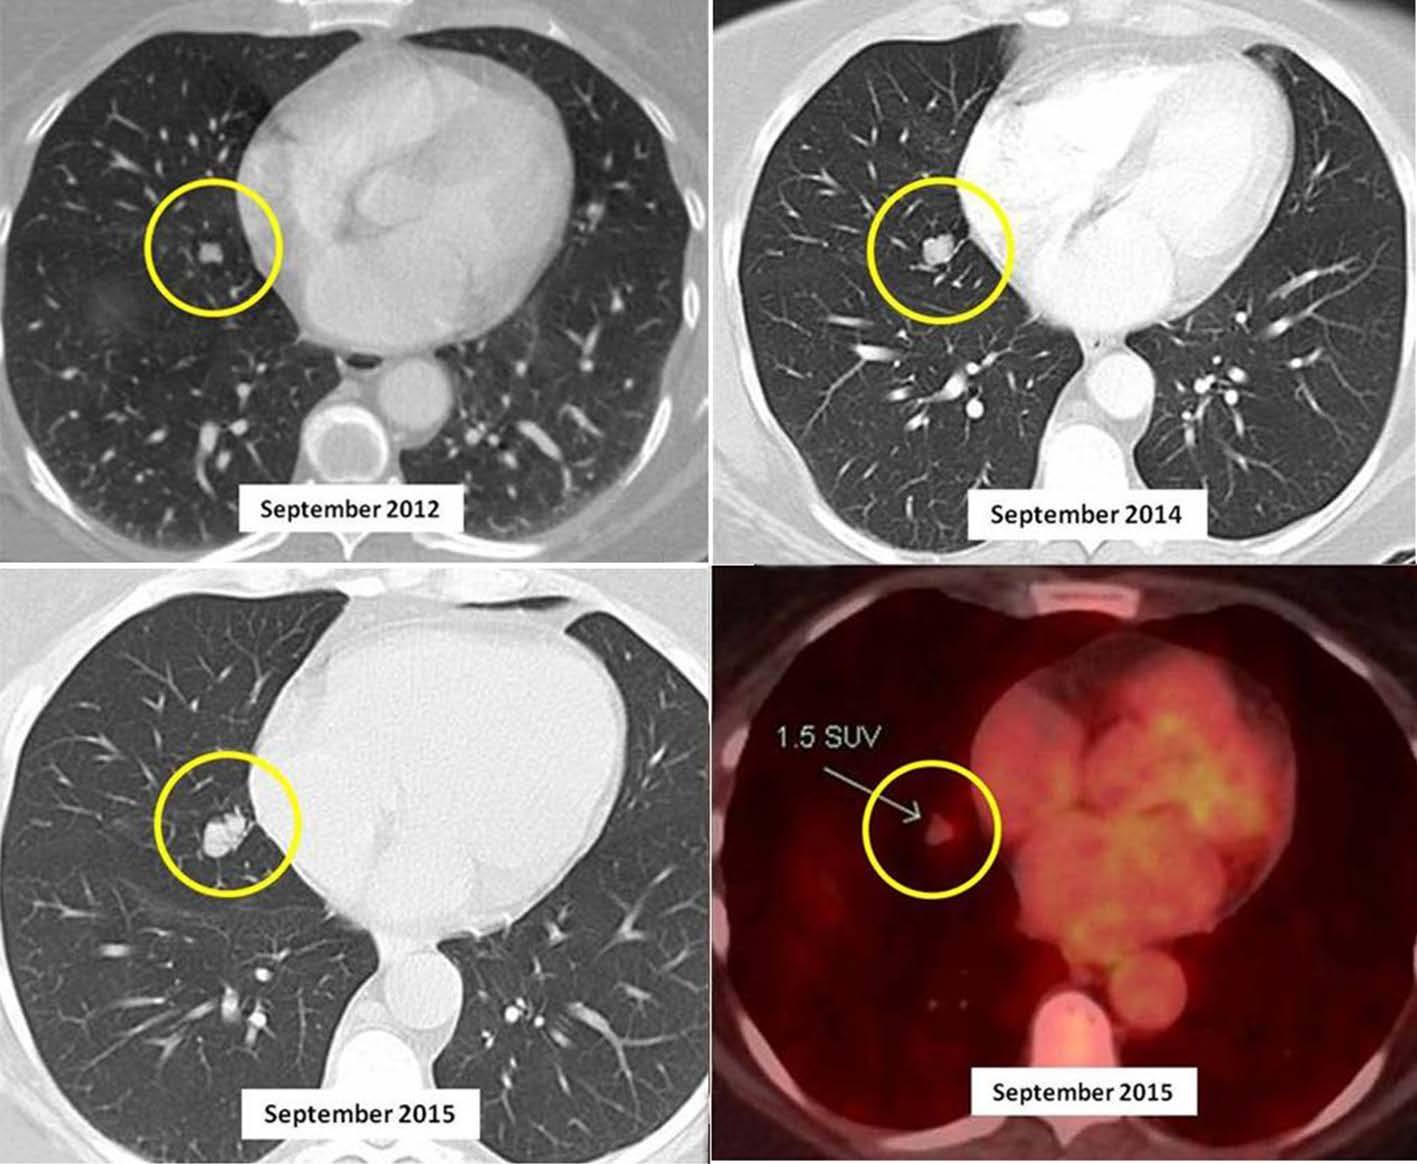

来源:Case Report: Do we really care about incidental lung nodules?

上图是典型的肺部结节在胸部 CT 随访中的进展。胸部 CT 扫描(2012 年)显示,右肺黄圈处有一个界限分明的小肺结节;随后的胸部 CT 扫描随访(2014、2015 年)显示右中叶肺结节明显逐渐增大;右下图是右中叶肺结节的 PET-CT 图像。